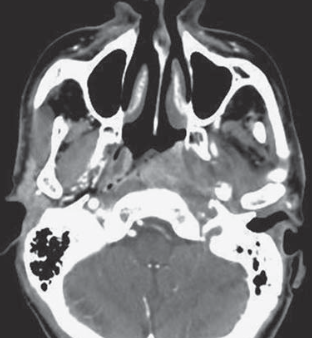

- Site de prédilectiond des carcinomes épidermoïdes naso-pharyngés